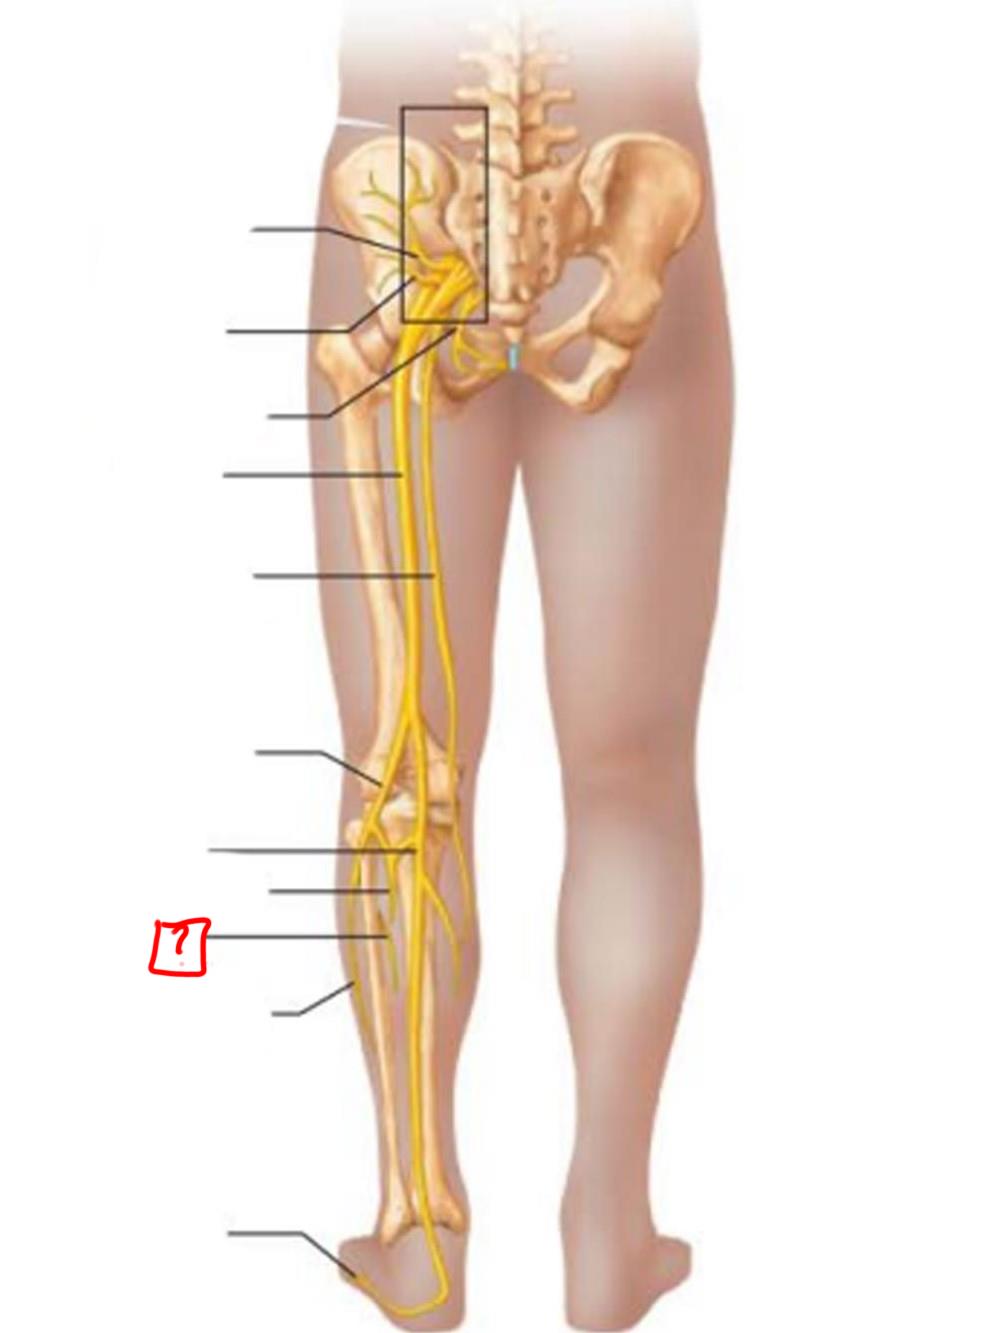

sciatic

posterior femoral cutaneous

common fibular

tibial nerve

sural (cut)

deep fibular

superficial fibular

plantar branches